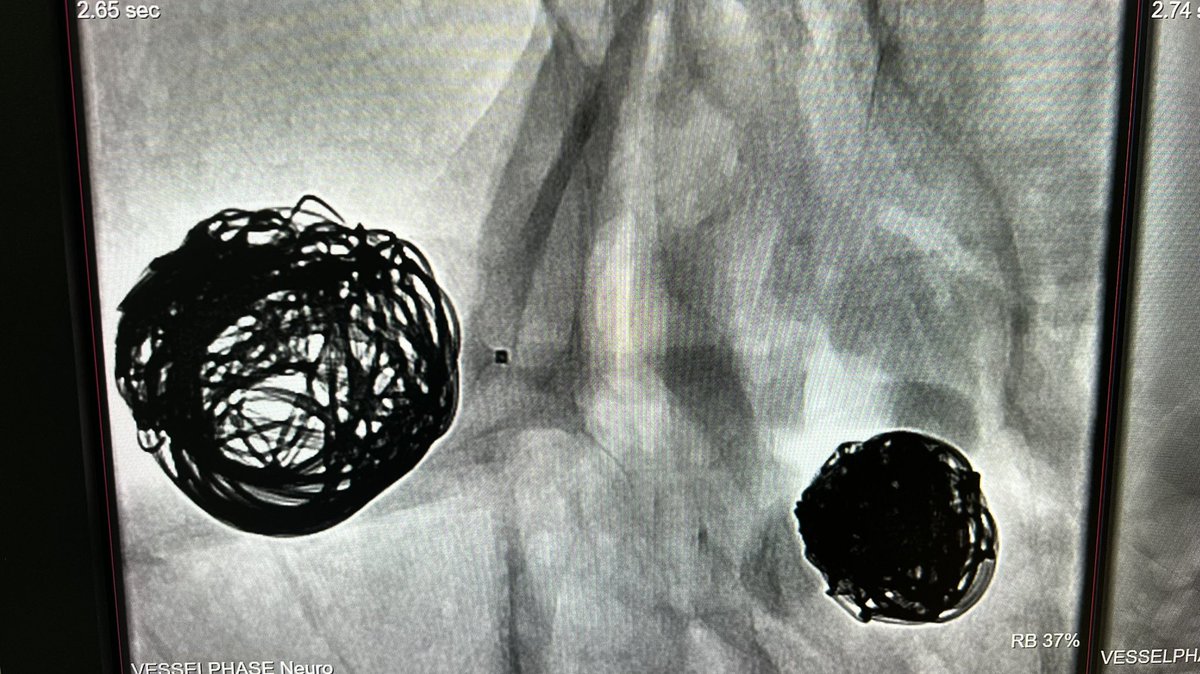

Wide-neck previously coiled/ruptured ACoA #aneurysm with bleb in neck. Perfect first Contour case in 2023 in the US🇺🇸 @IncCerus @PennNSG #cerebrovascular @cvsection #stasis #intrasaccular

1

4

20